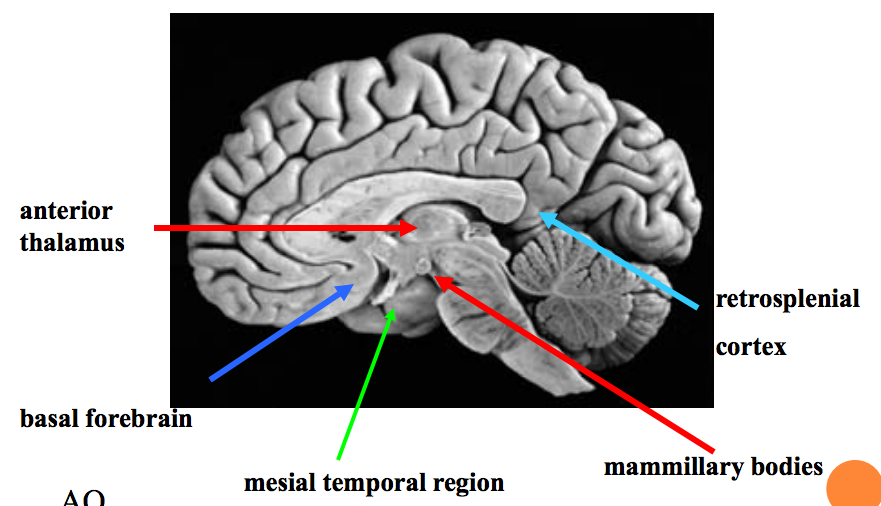

List some of the other midline structures (besides hippocampus) that are important in memory?

Anterior thalamus

Basal forebrain

Mesial temporal region

Mamillary bodies

Retrosplenial cortex